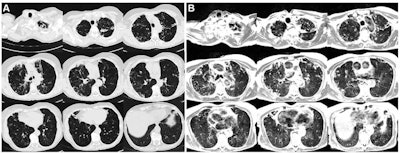

Axial multisection imaging yielded full lung coverage using (A) CT (reformatted to 0.8 x 0.8 x 6 mm) and (B) T2-weighted MRI (1.1 x 1.1 x 6 mm) in a 69-year-old woman with bronchiectasis, cavitary lesions, and scattered pulmonary nodules. Images and caption courtesy of the RSNA.Campbell-Washburn's team conducted their study between November 2018 and December 2019 and included 24 participants with lung abnormalities; they compared breath-triggered T2-weighted turbo spin-echo MRI at 0.55 tesla with CT scans. The researchers assessed abnormal findings identified with MRI and CT using the kappa coefficient.

The researchers were able to obtain effective lung MR images with an average acquisition time of 11 minutes, and MRI detected a range of lung conditions comparably to CT (measured by kappa coefficient).

Diffuse disease (ground-glass opacities and tree-in-bud nodules) were the hardest to identify on low-field strength MRI, the authors noted.

"This discrepancy might be attributable to the difference in respiratory position between MRI and CT, or it may demonstrate the suboptimal capability of MRI to detect subtle processes causing tree-in-bud and ground-glass opacities," they wrote.